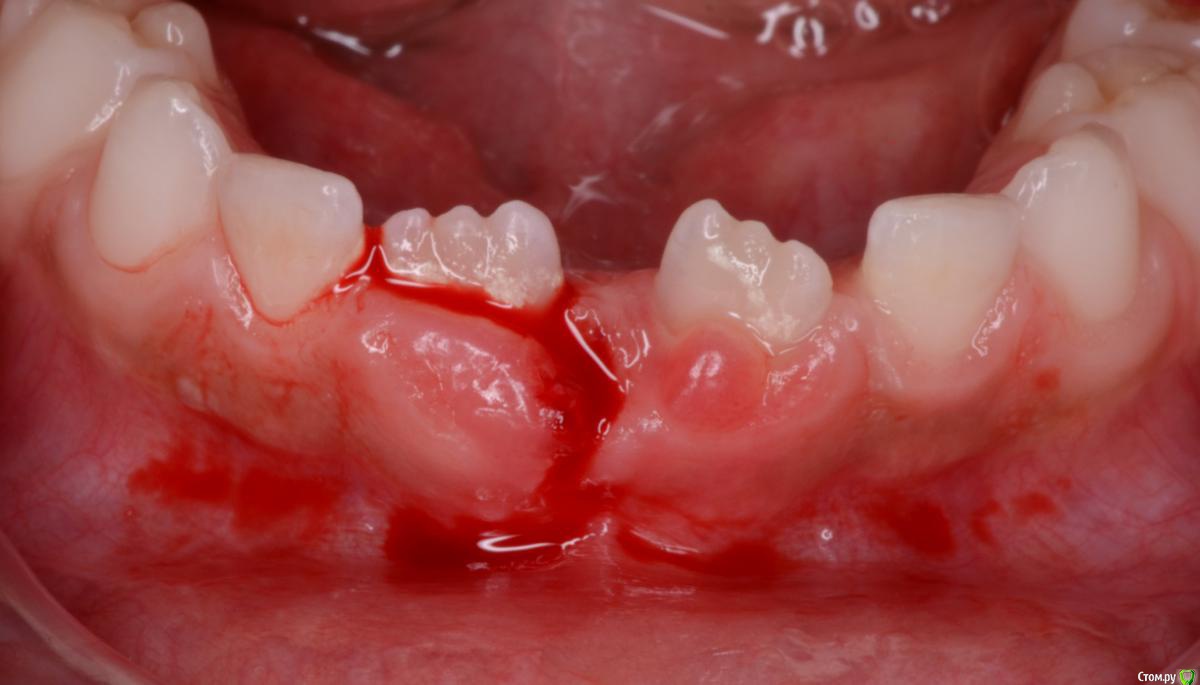

CRAZYDUCK Опубликовано 14 февраля, 2020 Автор Поделиться Опубликовано 14 февраля, 2020 Красивое красное фото ! Резорбция корня временного Резца почти полная , но уходить он не хочет . Удалила и жлеммна осмотр через месяц . Ссылка на комментарий